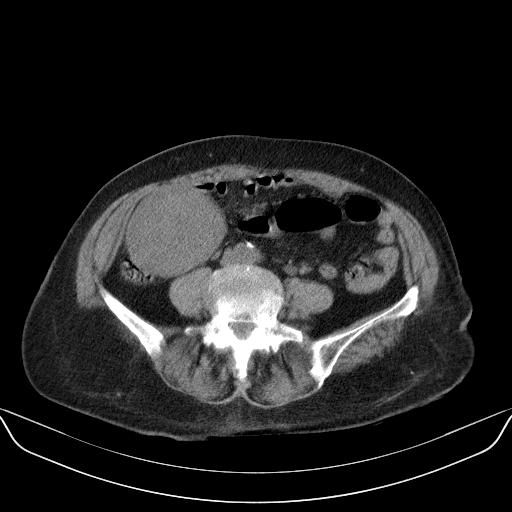

以下是引用yuhongjun在2010-3-12 6:32:00的发言:[br]回肠末端间质瘤,不除外阑尾粘液囊腺瘤,臀部注射性肉芽肿钙化. [br] [br]